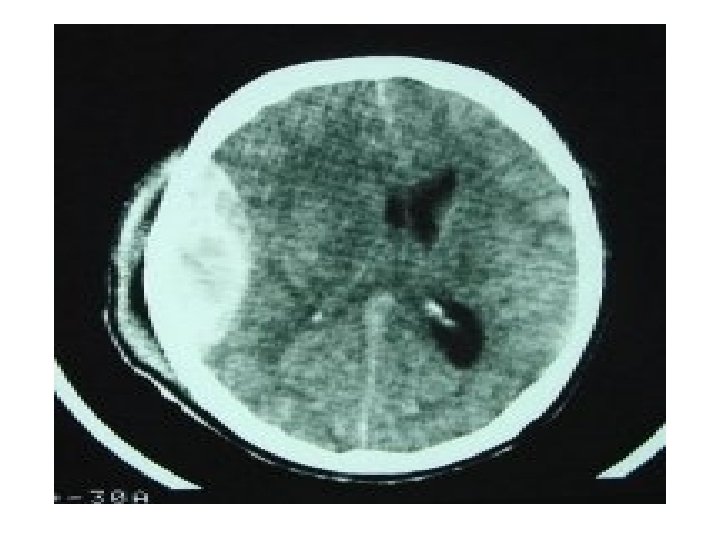

Acute Subdural hematoma

Chronic Subdural hematoma